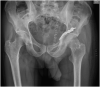

Traumatic hip dislocations typically result of high-energy trauma and frequently involve young patients. The obturator dislocation is not a common condition and rarely combined with acetabular fracture. We report a rare case of a 48-year-old male patient with a trauma of the left hip following a car-vs-car frontal accident. He presented with an obturator hip dislocation combined with ipsilateral quadrilateral plate fracture. The patient underwent a clinical and imaging evaluation to identify the acetabular fracture dislocation. The CT scan showed a severe dislocation of the acetabular medial wall. Closed reduction under conscious sedation was performed in Emergency Department. The patient underwent open reduction and internal fixation. During surgery, obturator nerve was entrapped inside the fracture rim and then it was released. No intra-operative complications were observed. The patient was followed, with accurate clinical and radiological follow up assessments for 24 months reporting excellent clinical outcomes according to Oxford Hip Score (47/48 points), a good hip range of motion and a complete recovery of basic activities of daily living. After two years of follow-up, no evidence of femoral head necrosis was reported and the patient returned to sport activity.